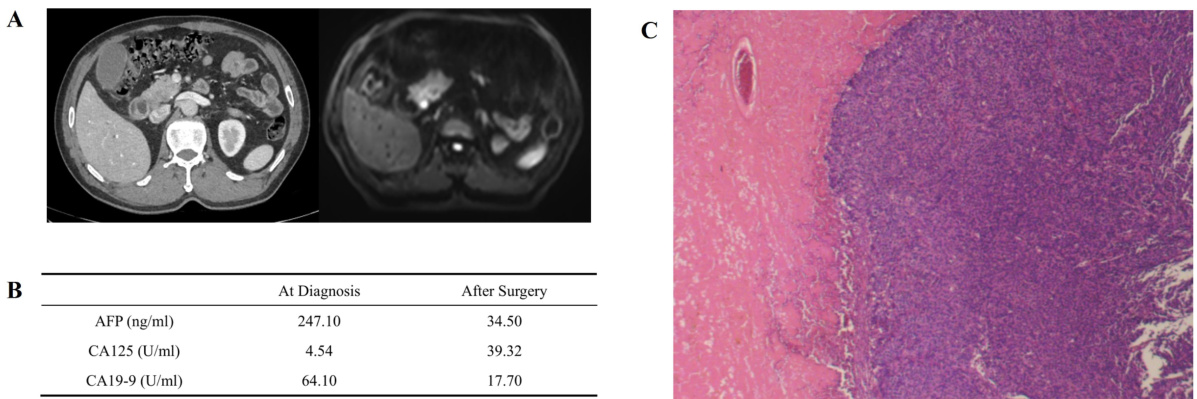

影像学提示病灶增大,肿瘤指标却离奇下降?警惕罕见胰腺癌诊疗中的“烟雾弹”

病史摘要:61 岁男性患者,因黄疸 10 天于 2024 年 8 月就诊,不伴其他消化道症状。既往有控制良好的高血压病史,无其他慢性疾病史及癌症家族史。 诊疗过程:入院影像学检查发现胰头占位,血清 AFP 和 CA19 - 9 升高,MDT 评估为可切除胰腺癌,行根治性胰十二指肠切除术,术后病理确诊为胰腺腺泡细胞癌。术后出现胰瘘、腹腔感染及新冠感染等并发症后康复。2024 年 11 月